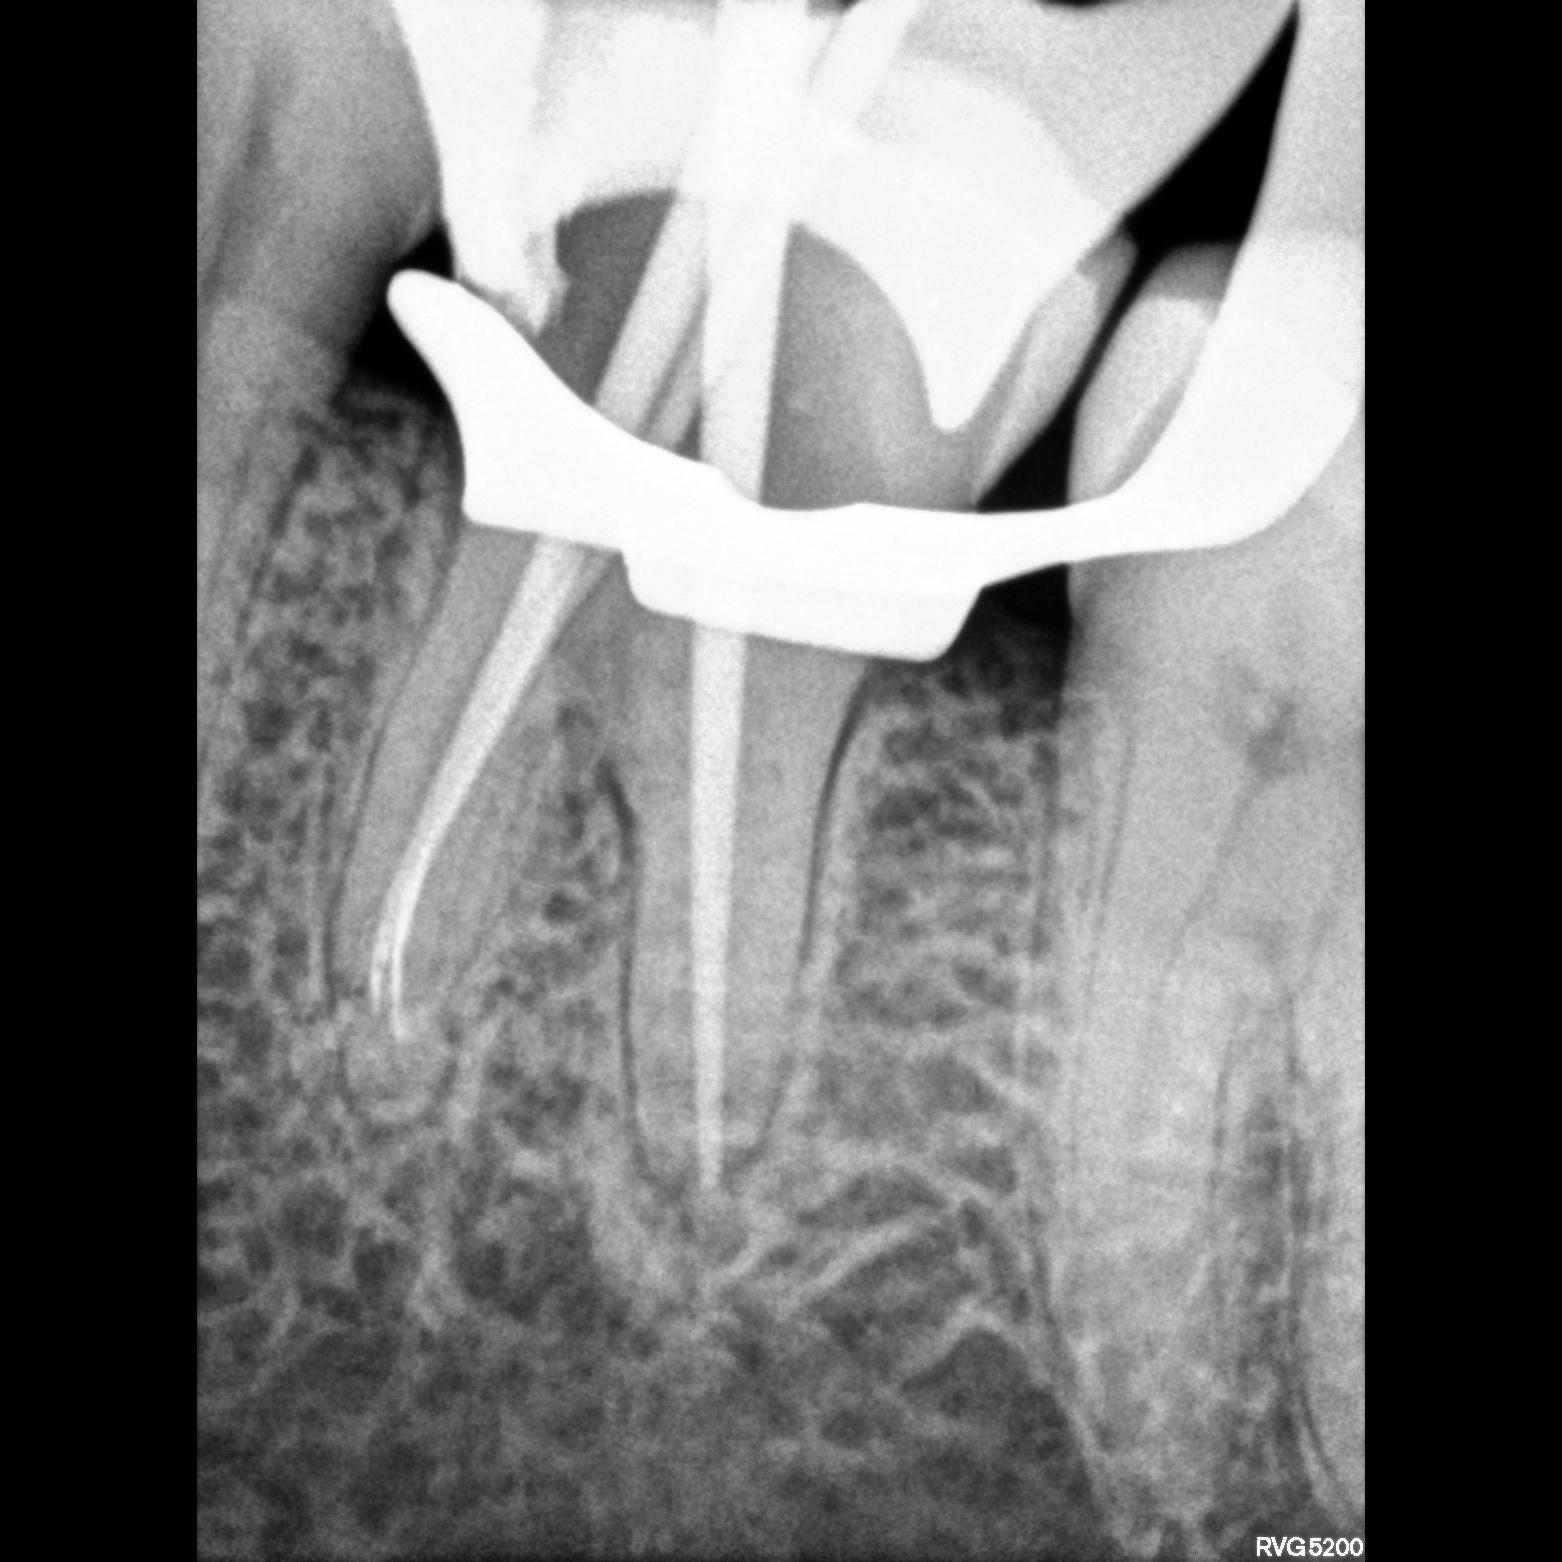

Smile Brighter with DHAANYA’S dental clinic ! Your Trusted Partner in Dental Care ✨ Comprehensive Dental Services for the Whole Family ✨ From routine checkups to advanced treatments, we provide a wide range of dental services to meet your needs. Our Services Include: - General Dentistry: Cleanings, exams, fillings, and more. - Cosmetic Dentistry: Whitening, veneers, and smile makeovers. - Orthodontics: Braces, clear aligners, and pediatric orthodontics. - Restorative Dentistry: Crowns, bridges, dentures, and implants. - Emergency Dentistry: Same-day appointments for dental emergencies. --- Why Choose Us? - Expert Care: Our team of experienced dentists and hygienists is dedicated to providing you with top-quality care. -Comfortable Environment: We prioritize your comfort with state-of-the-art equipment and a warm, welcoming atmosphere. - Affordable Solutions: We offer flexible payment plans and accept most insurance providers. - Convenient Hours: Evening and weekend appointments available